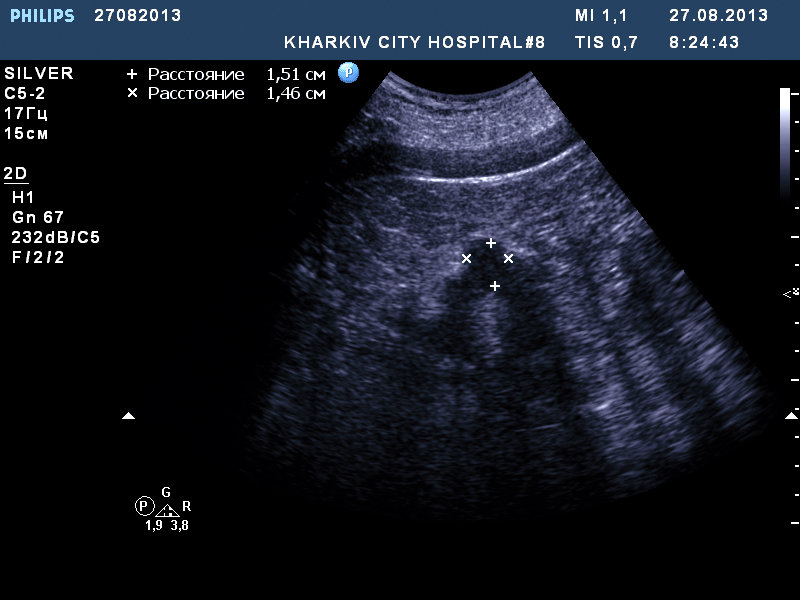

собственно такая картина.

если мой прицел не сбился, вероятно ПКР.

Рекомендовал КТ.

Сосудистый рисунок сохранен на сонограммах 1 и 2.